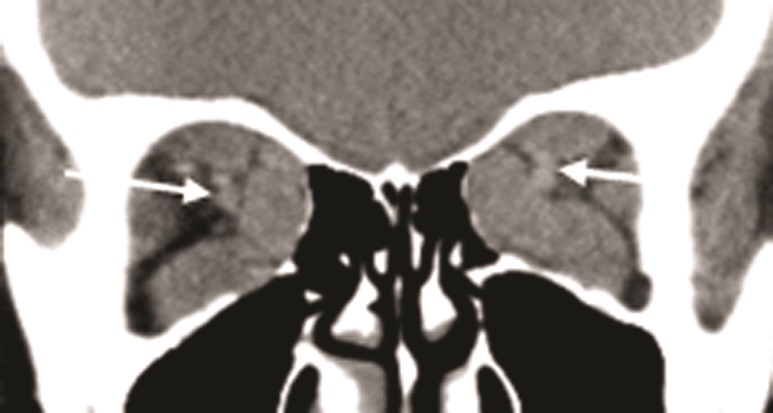

Рис. 7. МСКТ, корональная проекция: визуализируются увеличенные слезные железы (белые стрелки)

По нашим данным, у пациентов с отечным экзофтальмом в 33% случаев в процесс вовлекается слезная железа. Она увеличивается в объеме и может смещаться к наружному краю верхней орбитальной стенки, вызывая асимметрию положения век. При этом в области верхнего века может пальпироваться опухолевидное образование. Вовлечение в патологический процесс слезной железы сопровождается усилением слезопродукции и появлением слезотечения. По мере увеличения проптоза и ширины глазной щели компенсаторные возможности слезной железы истощаются и развивается синдром «сухого» глаза [12]. Томографические исследования установили вовлечение слезной железы в аутоиммунное воспаление в 38% случаев. У этих пациентов присутствовали признаки дакриоаденита. Таким образом, слезную железу, наряду с РБК и ЭОМ, можно считать органом-мишенью аутоагрессии. Вовлечение слезной железы в аутоиммунный процесс сопровождалось достоверным увеличением длины и ширины орбитальной части глаза (рис. 7).